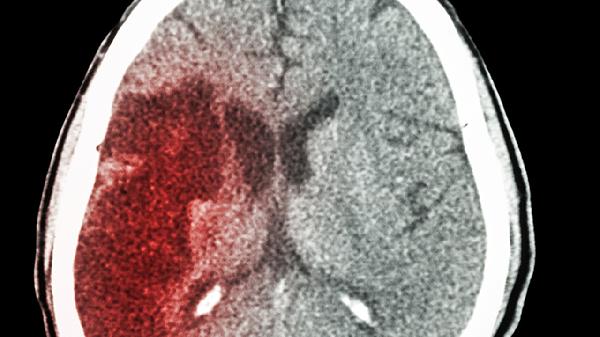

突发单侧肢体无力、言语含糊或剧烈头痛可能预示脑卒中发作。部分患者会出现短暂性脑缺血发作,表现为一过性黑蒙或肢体麻木,这些症状即使自行缓解也需24小时内急诊评估。